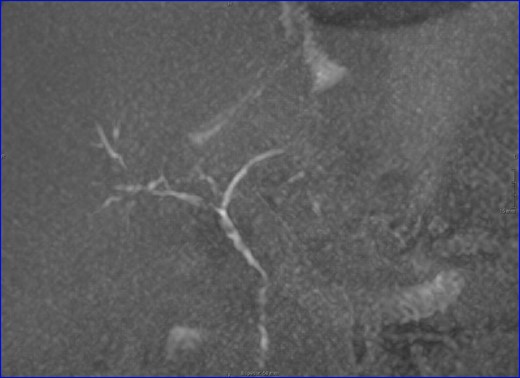

On the seventh postoperative day (POD), discharge of bile contents was observed by the abdominal drainages. Therefore, given the suspicion of ischemic cholangiopathy (IC) and the poor clinical situation of the patient, a transparietohepatic cholangiography was performed for diagnostic and therapeutic intention, demonstrating a destructuring of the intra- and extrahepatic bile duct compatible with ischemic cholangiopathy, so an internal–external transhepatic drainage was inserted. After clinical improvement, the study was completed with an MRI that showed signs of multiple hepatic infarctions and diffuse IC (Fig. 2).

MRI: biliary tract, multiple stenosis. ischemic cholangiopathy.